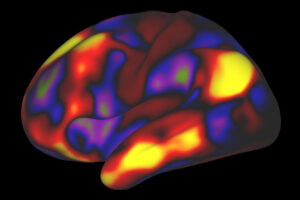

People with sleep apnea wake up tired in the morning, no matter how many hours they actually sleep. The condition causes them to briefly stop and restart breathing dozens or even hundreds of times a night. Even though such breathing interruptions often don’t awaken those with apnea, they prevent them from sinking into deep, refreshing […]